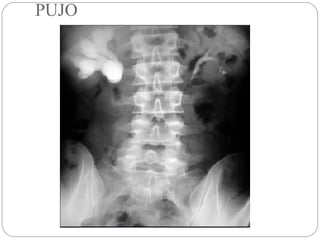

PUJO

The balloon ona string sign This sign refers to the appearance of a high and somewhat eccentric exit point of the ureter from a dilated renal pelvis and is a typical finding of ureteropelvic junction obstruction

• 116.